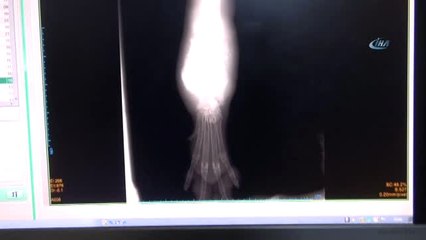

- Çocukların Paşa'ya koşması - Çocukların Paşa'yı sevmesi - Nevin Peker'in Paşa ile ilgilenmesi - Paşa'nın mamasını yemesi - Paşa'nın bir başka köpekle oyun oynaması - Nevin Peker'in konuşması - Peker ve Çocukların Paşa ile oyun oynaması - Ece Peker'in Konuşması - Köpeğin eski yaralı ve uyuz halleri (ARŞİV)Otomobile bağlanarak sürüklenen köpek sağlığına kavuştu - İzmir 'in Bergama ilçesinde, otomobilin arkasına iple bağlanıp sürüklendiği görüntülerin sosyal medyada paylaşılmasının ardından hayvanseverler tarafından sahiplenilen "Paşa" iyileşti - Yeni sahibinin bakım ve desteğiyle eski günlerine kavuşan Paşa, hem bakıcısının hem de çocukların sevgilisi haline geldi - Nevin Peker: - "Paşa'yı ilk bulduğumuzda ileri derecede uyuzluğu ve çok zayıflığı vardı. Sürüklenmeden kaynaklı uzuv kaybına yakın travmalar yaşamıştı. Şu anda kilosuna yeniden kavuştu. Sağlığı yerinde ve travmayı atlattı"İZMİR (AA) - METİN AYDEMİR - İzmir 'in Bergama ilçesinde, mart ayında otomobilin arkasına iple bağlanıp sürüklenen "Paşa" isimli köpek, hayvanseverlerin desteğiyle yeniden sağlığına kavuştu.Bergama - Kozak yolu üzerinde bir köpeğin otomobile iple bağlanıp sürüklendiği görüntülerin sosyal medyada paylaşılmasının ardından Bergama Hayvanları Koruma ve Yaşatma Derneği (BERHAYKO) üyeleri Paşa'yı bulup veterinere götürdü.Olaydan sonra yasal yollara başvurarak köpeği sahibinden alan dernek üyeleri, Paşa'nın bakımını üstlendi.BERHAYKO üyesi olan Nevin Peker, köpeği sahiplendi ve Küçükkaya Mahallesi'ndeki bir depoda ona yuva yaptı.Peker'in ailenin bir üyesi olarak gördüğü Paşa, kısa zaman içerisinde eski sağlığına kavuşarak bahçede çocuklarla koşup oyunlar oynamaya başladı.br - "O cana yakın ve oyunbaz bir can"Nevin Peker, AA muhabirine yaptığı açıklamada, köpeğin eski sağlığına kavuşmasından dolayı mutlu olduğunu söyledi.brbrOnu ailece çok sevdiklerini ifade eden Peker, "Paşa'yı ilk bulduğumuzda ileri derecede uyuzluğu ve çok zayıflığı vardı. Sürüklenmeden kaynaklı uzuv kaybına yakın travmalar yaşamıştı. Şu anda Paşa, kilosuna yeniden ulaştı. Sağlığı yerinde ve travmayı atlattı." şeklinde konuştu.brPaşa ile çok mutlu olduklarını, onun artık ailelerinin bir ferdi olduğunu kaydeden Peker, "İyi ki sahiplendik onu. O bizim hayatımıza girdikten sonra gezmelerimiz de değişti, onunla birlikte eğleniyoruz. O cana yakın ve oyunbaz bir can. Böyle de devam edeceğiz inşallah." dedi.brÇocukları Ece ve Efe'nin Paşa ile iyi vakit geçirdiğini dile getiren Peker, şöyle konuştu:"Paşa, çocuklarla oynamayı, koşmayı çok seviyor. Onları yalıyor, önce bir korkuyorlar, sonrasında sarılıyorlar birlikte. Mamalarını yiyor, suyunu içiyor. Tuvalet eğitimi var Paşa'nın olduğu yere yapmıyor. Ece, Efe, Paşa'nın üstüne çıksa bile hiçbir şekilde onlara tepki vermiyor. Çok cana yakın bir can. Bizimle yaşamaya devam edecek."Peker, kaza geçirmiş ya da zarar vereceği düşünülen bir hayvan görüldüğü zaman 153'ün aranarak durumun belediye ekiplerine bildirilmesini istedi.Nevin Peker'in 8 yaşındaki kızı Ece Peker de Paşa ile çok mutlu olduğunu belirterek, "Paşa'yı çok seviyorum, o da beni seviyor." diye konuştu.